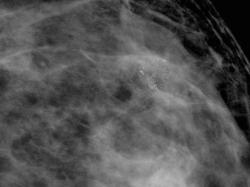

привожу случай снова.В верхне-наружном квадранте левой молочной железы отмечаются сгруппированные микарокальцианты без явной принадлежнсти к узловому образованию

Пациентка прооперирована. Гистология по cito: инфильтрирующий рак с участками слизистого рака.

Спасибо за случай. По большому счету, конечно, кое, что исчезло. Но большинство иллюстрации наших пользователей продублировано и никуда не делось. Имею вопрос. Рак ьыл обнаружженов зоне микрокальцинатов или нет?

Да сначала планирвалась скторальная резекция.При cito вой гистологии рака выполнена мастэктомия.